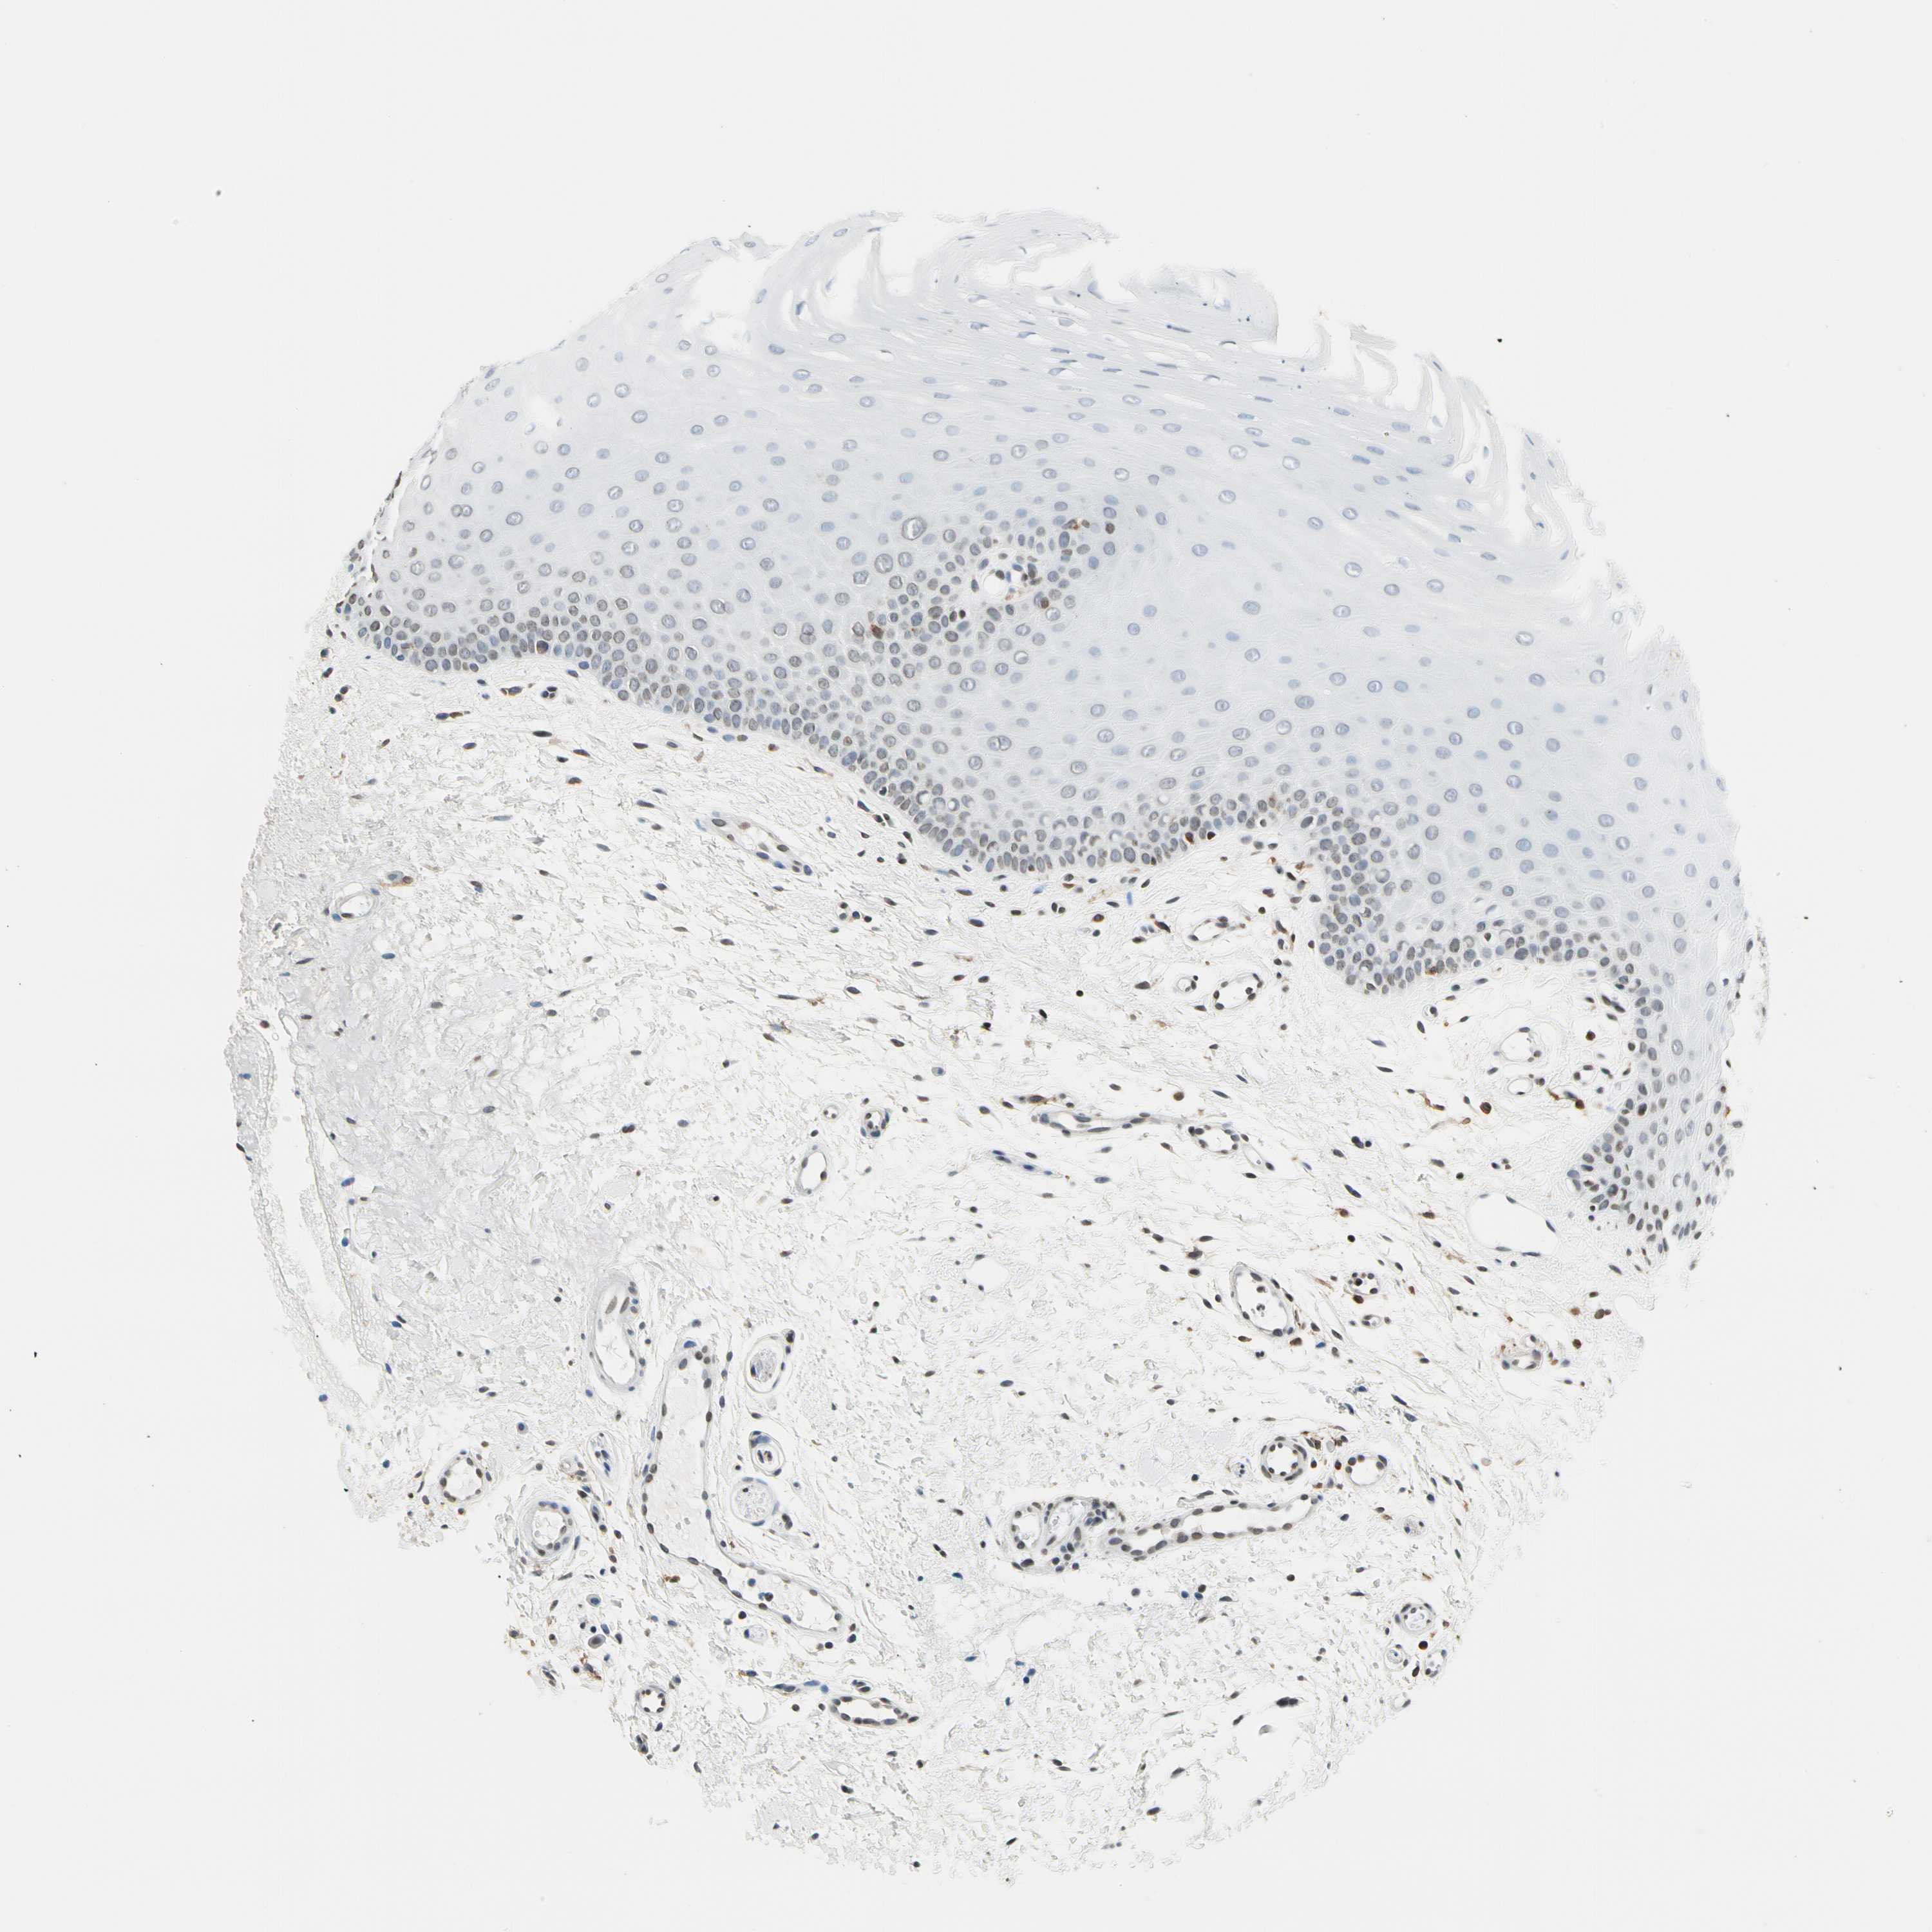

ORAL MUCOSA - Antibody stainingi

Antibody staining in the annotated cell types in the current human tissue is reported as not detected, low, medium, or high, based on conventional immunohistochemistry profiling in selected tissues. This score is based on the combination of the staining intensity and fraction of stained cells.

Each image is clickable and will lead to virtual microscopy that enables deeper exploration of all samples and also displays staining intensity scores, fraction scores and subcellular localization as well as patient and tissue information for each sample.

Antibody HPA007641Antibody CAB022464

Squamous epithelial cells Not detectedMedium